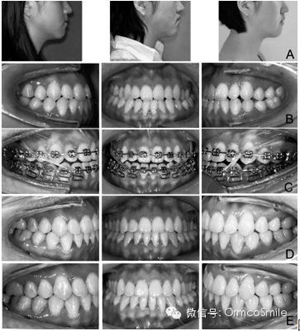

圖1 實(shí)驗(yàn)組患者示例。

A 治療前、治療結(jié)束、保持一年后的側(cè)貌;

B 治療前口內(nèi)像;

C 治療中口內(nèi)像;

D治療結(jié)束時(shí)口內(nèi)像;E保持一年后的口內(nèi)像